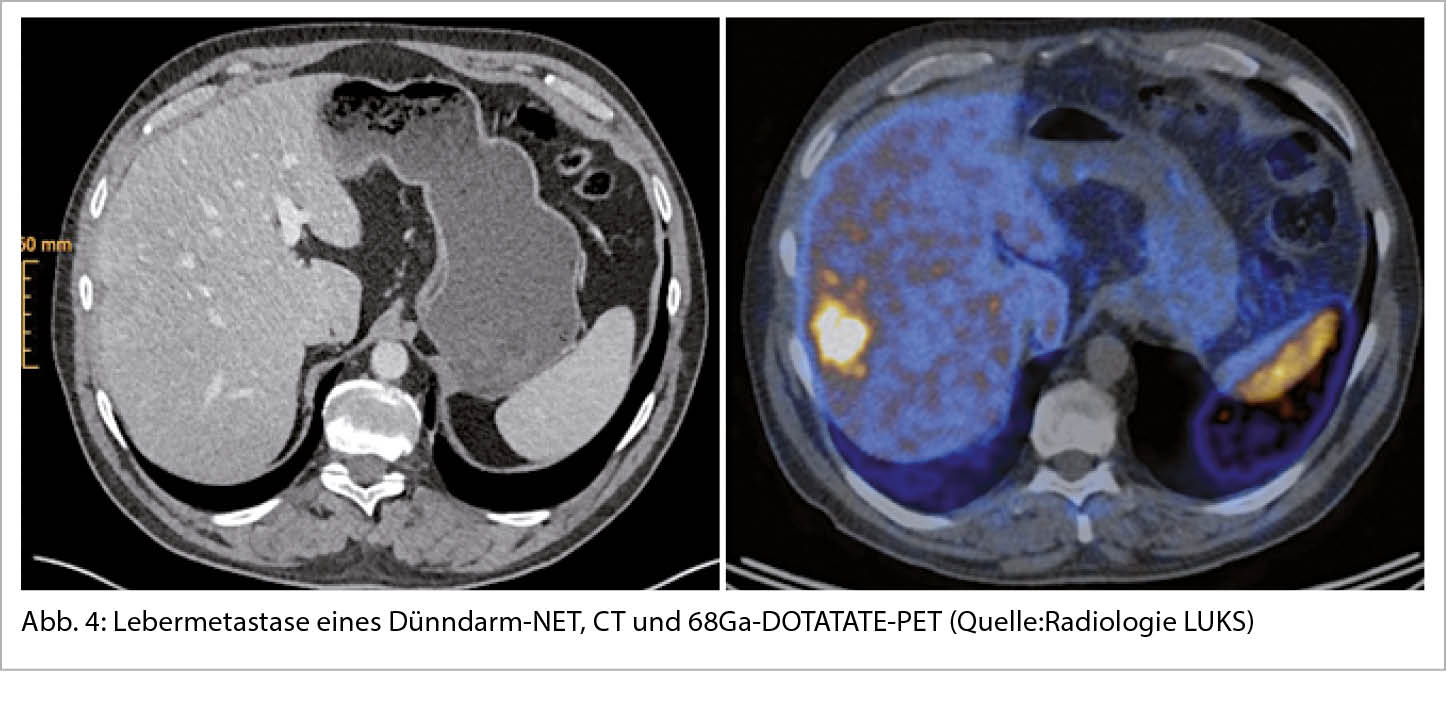

In der bildgebenden Diagnostik spielen die Schnittbildverfahren wie CT und MRI eine grundlegende Rolle sowohl für die Darstellung des Primarius als auch der Metastasierung. Mit der Computertomographie wird das Ausmass der Metastasierung, vor allem in der Leber oftmals unterschätzt, weshalb die MRI-Untersuchung der Leber mit einer deutlich höheren Sensitivität komplementär eingesetzt werden kann (14). Die Mehrheit der gut-differenzierten NET exprimiert Somatostatinrezeptoren (SSTR) an ihrer Zelloberfläche, vor allem den Somatostatinrezeptor-2 (SSTR2) (15). Mit der funktionellen Bildgebung, dem 68Ga-DOTATATE-PET gelingt nicht nur ein besseres Erfassen unbekannter Primärtumoren und Staging (auch ossärer und peritonealer Metastasen, Abbildung 4), sondern auch eine Darstellung des SSTR2, dem wichtigsten therapeutischen Target (16). Bei zunehmender Agressivität des Tumors (NET G3 oder gar NEC) nimmt die Somatostatinrezeptorexpression ab und die FDG-Affinität zu, sodass das FDG-PET als Ergänzung oder anstelle des DOTATATE-PET eingesetzt werden soll. Es wird empfohlen, anatomische und funktionelle Bildgebung in der Primärdiagnostik zu kombinieren.